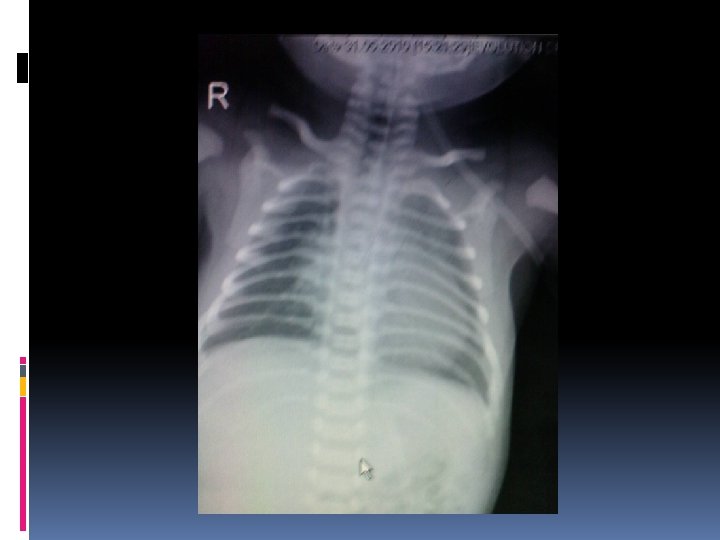

Case discussion: case I A male premature baby, birth weight 2. 1 kg Respiratory distress with heart murmur No dysmorphic feature Normal S 1, S 2 with SEM gr 2/6 at LPSB

Investigation Echocardiography Single functioning morphologic RV, DIRV, DORV, rudimentary LV, large bulboventricular foramen Mild MS, No AS, No PS hypoplastic aortic arch 3 mm, severe Co. A 2. 5 mm, PDA 3. 3 mm CTA heart

Operation and findings Severe coarctation of the aorta and hypoplastic aortic arch Hypoplastic LV Deep hypothermia + circulatory arrest Resection and end-to-end anastomosis Pulmonary artery banding